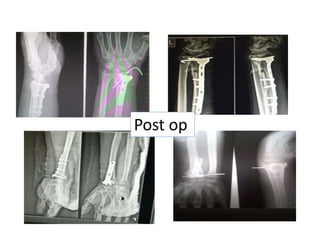

Post op

Post op protocols •All patients are immobilised for 2 weeks for soft tissues to heal • After suture removal advised mobilisation • No wt bearing and strenous activities upto radiological healing • Regular follow ups